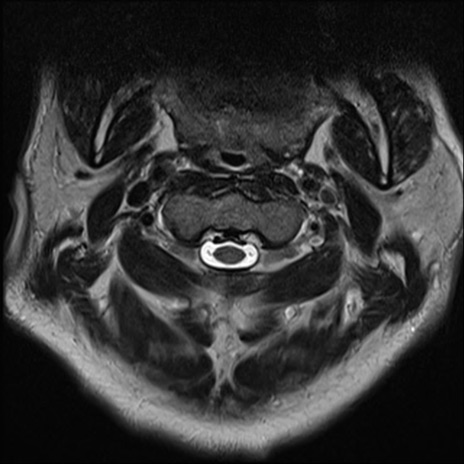

【整形】TIPS症例7 頚椎MRI T2WI(横断像)

頚椎MRI

矢状断像と横断像